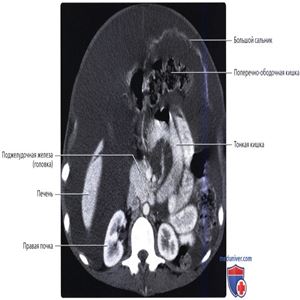

Серповидная связка поддерживает печень с передней брюшной стенки. Большой сальник лежит между кишечником и передней брюшной стенкой.

Внутрибрюшинные органы, такие как печень, поперечно-ободочная кишка и тонкая кишка взвешены в асцитической жидкости, при этом она не влияет на положение забрюшинных органов, таких как почки и поджелудочная железа.